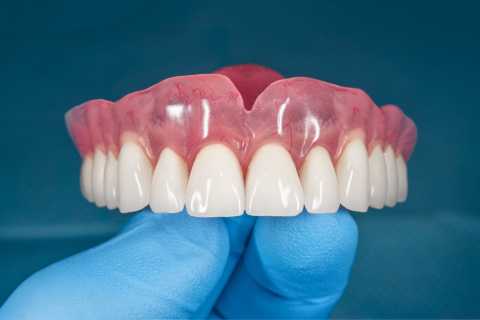

Proteza scheletata superioara pe telescoape si inferioara pe capse

Cazul 21: Proteze scheletate cu sisteme speciale de prindere

Protezele scheletale cu sisteme speciale de prindere reprezintă soluții de tratament care necesită înaltă specializare atât a medicului stomatolog, cât și a tehnicianului dentar, fiind recomandate în special pacienților cu edentații extinse, însă care prezintă încă suficienți dinți naturali rămași pe care se pot realiza astfel de lucrări dentare.